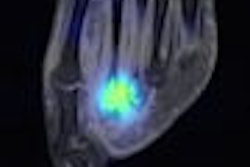

In molecular imaging news, Finnish researchers have found favorable results using PET with carbon-11-labeled Pittsburgh Compound B (C-11 PiB) for assessing beta-amyloid brain deposits. The study results support the use of C-11 PiB in evaluating these deposits in patients with mild cognitive impairment, Alzheimer's disease, or normal-pressure hydrocephalus (NPH), according to the Finnish study team.

The researchers also believe that the technique may have a potential role as a diagnostic aid for early Alzheimer's disease. Learn more by clicking here, or visit our Molecular Imaging Digital Community at molecular.auntminnie.com.